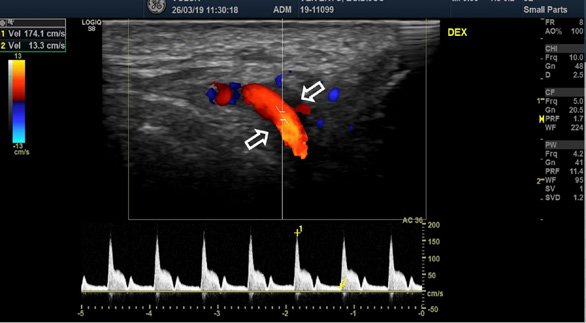

The blood test showed significantly increased CRP (208 mg/l), ESR (68 mm/h) and leucocytosis (12.30*10^9/l). Color-coded duplex sonography revealed the concentric hypoechoic thickness of the walls in both superficial temporal arteries, known as the ‘halo’ sign, which is a specific ultrasound finding in the case of GCA. The blood flow velocities of the superficial temporal artery were increased by approximately 200 cm/s bilaterally (Fig. 1 A, B).

Color-coded duplex sonography revealed the typical ultrasound findings of temporal arteritis: the ‘halo sign’ as the dark area around the superficial temporal artery lumen probably due to arterial wall oedema (white arrows) with increased blood flow velocities on the right (A) and left (B) sides.